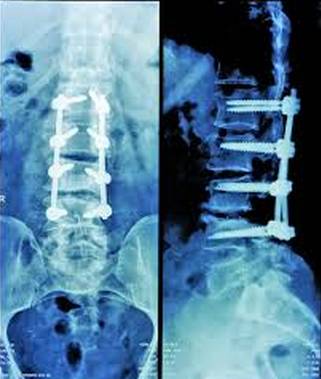

3、研發(fā)用于脊柱固定的可生物降解聚合物

一種海綿狀聚合物材料,能幫助修復脊柱

可生物降解的脊柱固定聚合物

可生物降解聚合物在骨骼愈合的過程中能被人體自然吸收,并且能夠提高成骨細胞的功能,這種聚合物能夠幫助我們擺脫需要長期使用的脊柱穩(wěn)定器。同時當骨折長期不愈合時,這種聚合物能夠增進骨折愈合能力,從而避免因骨移植和使用內(nèi)外部設備發(fā)生的感染、過長時間住院和發(fā)病致死的情況。已有科研團隊開展了相關研究,希望能夠從根本上改變傳統(tǒng)的治療方式。